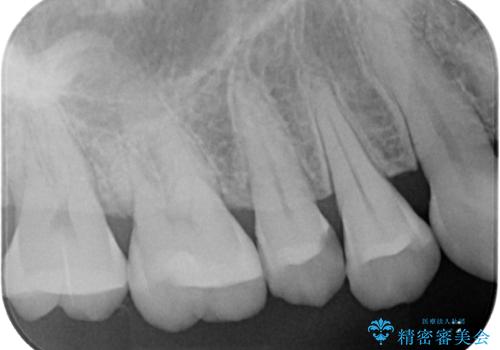

- 今回は、「右上の詰め物が欠けてしまった」という主訴で来院された、40代女性の患者さんの症例をご紹介します。

診察の結果、上顎右側第二小臼歯に装着されていた詰め物の一部が欠けている状態でした。一見すると小さな欠けに見えますが、詰め物が破損した部分はプラーク(歯垢)が非常に溜まりやすく、虫歯の再発リスクが高い状態になります。

まず、欠けていた詰め物と、その下に存在していた虫歯をすべて丁寧に除去しました。その後、適合性・耐久性・審美性に優れたセラミックインレーを用いて修復処置を行いました。